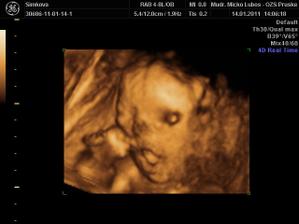

Naša princezná (v brušku...)

Stráááášne sa na ňu tešíme.......

je to mala herecka....ukazala nam vsetko....moc sa na nu uz tesime